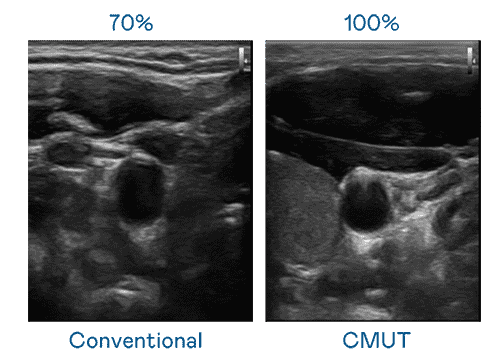

CMUT 技术是一种用电容式微机电元件来产生超音波讯号的技术。。与传统 PZT 压电式技术相比,,,CMUT 频宽增加 30%,,,,更宽频的超音波讯号让影像解析度大幅提升,,,,是实现高影像品质医疗超音波扫描、、、促进精准医疗发展的关键技术。。

大频宽带来超清晰影像

超音波影像的解析度高低,,首先取决于探头能发出的讯号频宽。。918.COM CMUT 可提供高清晰的超音波讯号,,,,提供高频宽、、高灵敏度、、、、影像纹理细节更高的超音波影像,,,协助医护人员缩短影像判读时间及利用精准的医疗影像进行诊断。。